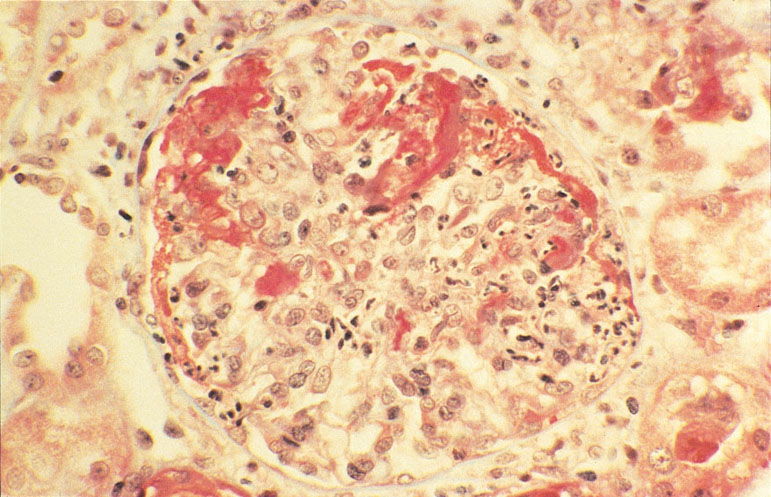

MALATTIA DI WEGENER – «Ancora migliore è la probabilità di guarire quando si tratta di una granulomatosi di Wegener» prosegue Raffaella Scorza. «Questo tipo di vasculite si risolve nella grande maggioranza dei casi con le cure di cui già disponiamo, purché siano iniziate presto e seguite nel migliore dei modi». Esiste però un piccolo gruppo di malati che non tollera i medicinali utilizzati contro questa rara forma di infiammazione dei piccoli vasi sanguigni che colpisce soprattutto i polmoni. «In questi casi, e solo in questi, è lecito lasciare la strada più sicura e provare a ricorrere ad altri mezzi, come i nuovi farmaci mirati» afferma Scorza. «Tra questi il rituximab si è spesso rivelato efficace». Spiera ha messo a confronto proprio questo prodotto, per alcune forme di artrite reumatoide oltre che per certi linfomi, con la ciclofosfamide, che rappresenta la cura standard in questa malattia. Quasi 200 malati con forme gravi di granulomatosi di Wegener e altre malattie molto simili, in nove diversi centri distribuiti negli Stati Uniti, hanno ricevuto l’uno o l’altro di questi medicinali, senza che né loro né i loro medici sapessero quale dei due principi attivi fosse contenuto nelle compresse. Gli effetti nei due gruppi sono stati sovrapponibili, solo con un leggerissimo vantaggio tra chi riceveva la nuova cura. «Si può dire che i due approcci siano quindi equivalenti» conclude il ricercatore statunitense. «Nelle persone in cui la ciclofosfamide provoca gravi effetti collaterali oppure in quelle ancora giovani che con il farmaco tradizionale rischiano di perdere la fertilità, il rituximab può quindi rappresentare una valida alternativa».